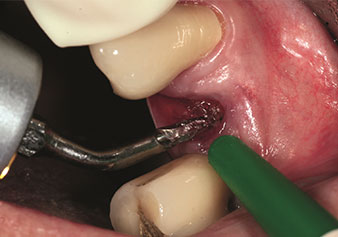

Rialzo del seno interno

W&H offre, inoltre, la soluzione perfetta per il rialzo del seno interno.

Dopo la preparazione dei seni mascellari con il corrispondente set di strumenti (Fig. 3), il nuovo strumento Z35P (Fig. 4) viene utilizzato per sollevare la membrana idrodinamicamente. Lo stesso set di strumenti può essere utilizzato anche per la preparazione piezochirurgica della sede dell’impianto in diametri crescenti (Figure 3 e 4 inserite grazie alla gentile concessione del Dott. Mario Kirste, Frankfurt/Oder).